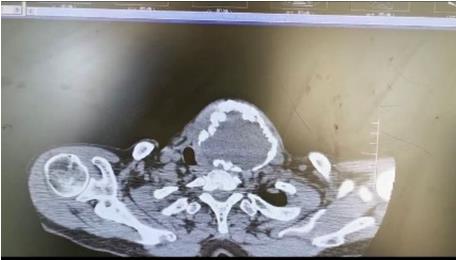

患者朱女士,68歲,頸部包塊呈進行性增大50年,來院后彩超及CT提示左側(cè)甲狀腺腫瘤已經(jīng)超過10公分并邊緣鈣化,氣管移位較明顯,腫瘤較大屬于罕見,不僅給患者造成心理陰影,還影響了正常生活,偶有憋悶不適,進食較大食物感哽咽不適。流動醫(yī)院下鄉(xiāng)義診時,發(fā)現(xiàn)包塊已經(jīng)很大了,影響到頸部的活動及飲食。醫(yī)生與患者及家屬溝通講解病情,表示我們?nèi)揍t(yī)院能治療。最后患者及家屬抱著試一試的態(tài)度來到延安大學咸陽醫(yī)院。

因逐漸長大的頸部嚴重影響飲食及活動,長達50年的折磨,患者身體很瘦、體質(zhì)差。甲狀腺腫瘤,瘤體大,手術創(chuàng)面較大,損傷喉返神經(jīng)及甲狀旁腺風險高,術后可能出現(xiàn)聲音嘶啞及低鈣抽搐等嚴重并發(fā)癥。同時瘤體長期對氣管的壓迫,致術后可能出現(xiàn)氣管軟化而發(fā)生致命性并發(fā)癥。

經(jīng)過普外二科趙建輝主治醫(yī)師及他們的團隊與麻醉科討論研究,認真分析頸部的解剖結(jié)構。確定最優(yōu)手術方案。于2022年1月14日上午在全身麻醉下行左側(cè)甲狀腺大部分切除+喉返神經(jīng)探查術,手術歷時1.5小時,順利結(jié)束,出血量較少,術中快速冰凍為結(jié)節(jié)性甲狀腺腫??紤]到創(chuàng)面較大,術中放一條引流創(chuàng)腔管,較好的保護了喉返喉上神經(jīng)及甲狀旁腺,手術成功。